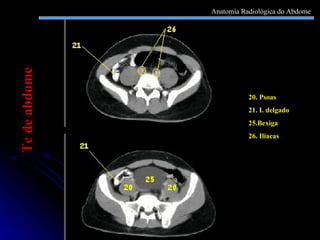

20. Psoas  21. I. delgado 25.Bexiga 26. Ilíacas Tc de abdome Anatomia Radiológica do Abdome